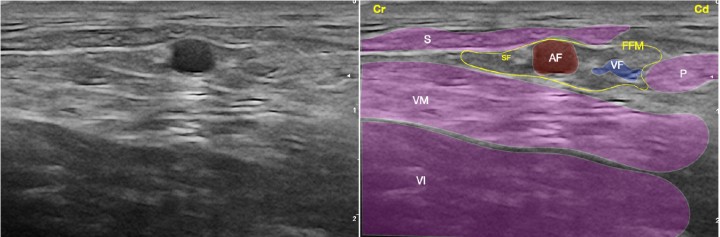

Figura 3

Imagen ecográfica del nervio safeno (rama sensitiva distal del nervio femoral) a nivel del fémur medio. Músculo sartorio (S), músculo vasto medial (componente del cuádriceps) (VM), músculo vasto intermedio (componente del cuádriceps) (VI), músculo pectíneo (P), fascia femoral media (FFM), arteria femoral (AF), vena femoral (VF), nervio safeno (SF). Cr: Craneal, Cd: Caudal.

Figura 8

(A) Posición del transductor y la aguja para el abordaje en plano del nervio safeno (rama sensitiva distal del nervio femoral) a nivel del fémur medio. (B) Imagen esquemática de las estructuras anatómicas y la aguja. Músculo sartorio (S), músculo vasto medial (componente del cuádriceps) (VM), músculo vasto intermedio (componente del cuádriceps) (VI), músculo pectíneo (P), fascia femoral media (FFM), arteria femoral (AF), vena femoral (VF), nervio safeno (SF). Cr: Craneal, Cd: Caudal.